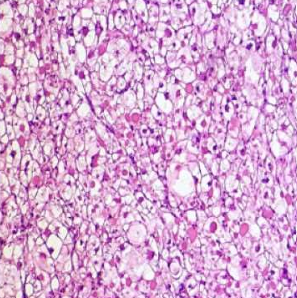

Arrhythmogenic right ventricular cardiomyopathy

Morphologically, the right ventricular wall is severely thinned owing to myocyte replacement by fatty infiltration and lesser amounts of fibrosis. (Microscopy)